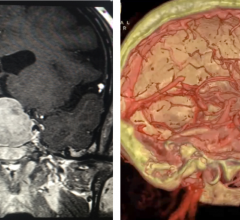

Software used to manipulate or enhance CT and MRI datasets, including MPR, and 3-D (3D) image reconstruction, perfusion imaging, 3-D printing, and procedural planning and procedural navigation.

February 14, 2019 — Medical imaging and visualization company Medivis officially unveiled SurgicalAR, its augmented ...